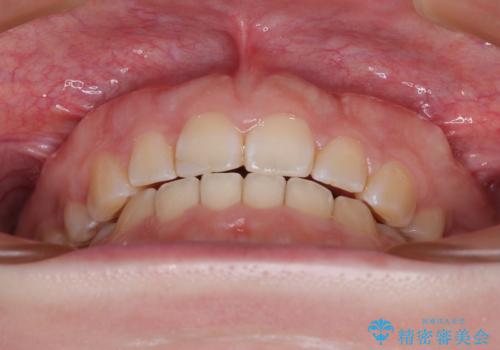

抜歯矯正を行ったことで、顎先のつっぱり感や口元の閉じにくさを解消することができました。

- 出っ歯と口の閉じにくさ、デコボコを気にして来院された患者様です。

口元の突出感を改善するため、上下左右第一小臼歯4本の抜歯を行い、ワイヤー装置による矯正治療を行うこととしました。